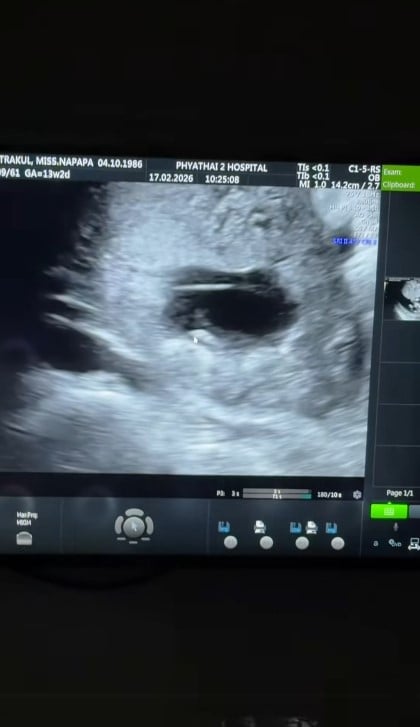

แม่แพทได้แชร์โมเมนต์สุดประทับใจ นาทีที่คนและคนรักได้เห็นหน้าสมาชิกใหม่ผ่านภาพอัลตราซาวด์ บรรยากาศเต็มไปด้วยความตื่นเต้นและอบอุ่น ทั้งคู่ต่างคอยซักถามคุณหมอด้วยความเอ็นดู ทั้งเรื่องเห็นนิ้ว เห็นปาก แถมยังแอบแซวเบบี๋ในท้องด้วยว่ากำลังทำท่าเหมือนก่ายหน้าผากอยู่ งานนี้แม่แพทก็เตรียมตัวดีสุด ๆ ขอคำปรึกษาคุณหมอเรื่องการนอนและการดูแลตัวเองอย่างใกล้ชิด

สาวแพทเปิดใจด้วยใบหน้ายิ้มแย้มสุดปลื้มปริ่มว่า ตอนนี้เตรียมตัวเป็นคุณแม่ลูกสองแล้ว โดยอายุครรภ์ปัจจุบันอยู่ที่ 3 เดือน ทางด้านว่าที่คุณพ่ออย่างหนุ่มพีก็เก็บอาการดีใจไว้ไม่อยู่ ยิ้มแก้มปริชี้ชวนดูใบหน้าเบบี๋ในภาพอัลตราซาวด์ไม่วางตายอมรับเลยว่าตอนนี้ดีใจมาก ๆ

ทันทีที่ประกาศข่าวดีออกไป โซเชียลก็แทบแตก แฟนคลับจำนวนมากต่างแห่เข้ามาคอมเมนต์แสดงความยินดีกับครอบครัวอย่างล้นหลาม แถมงานนี้เหล่านักสืบโซเชียลยังช่วยกันวิเคราะห์ภาพอัลตราซาวด์และแซวเบบี๋กันมากมาย